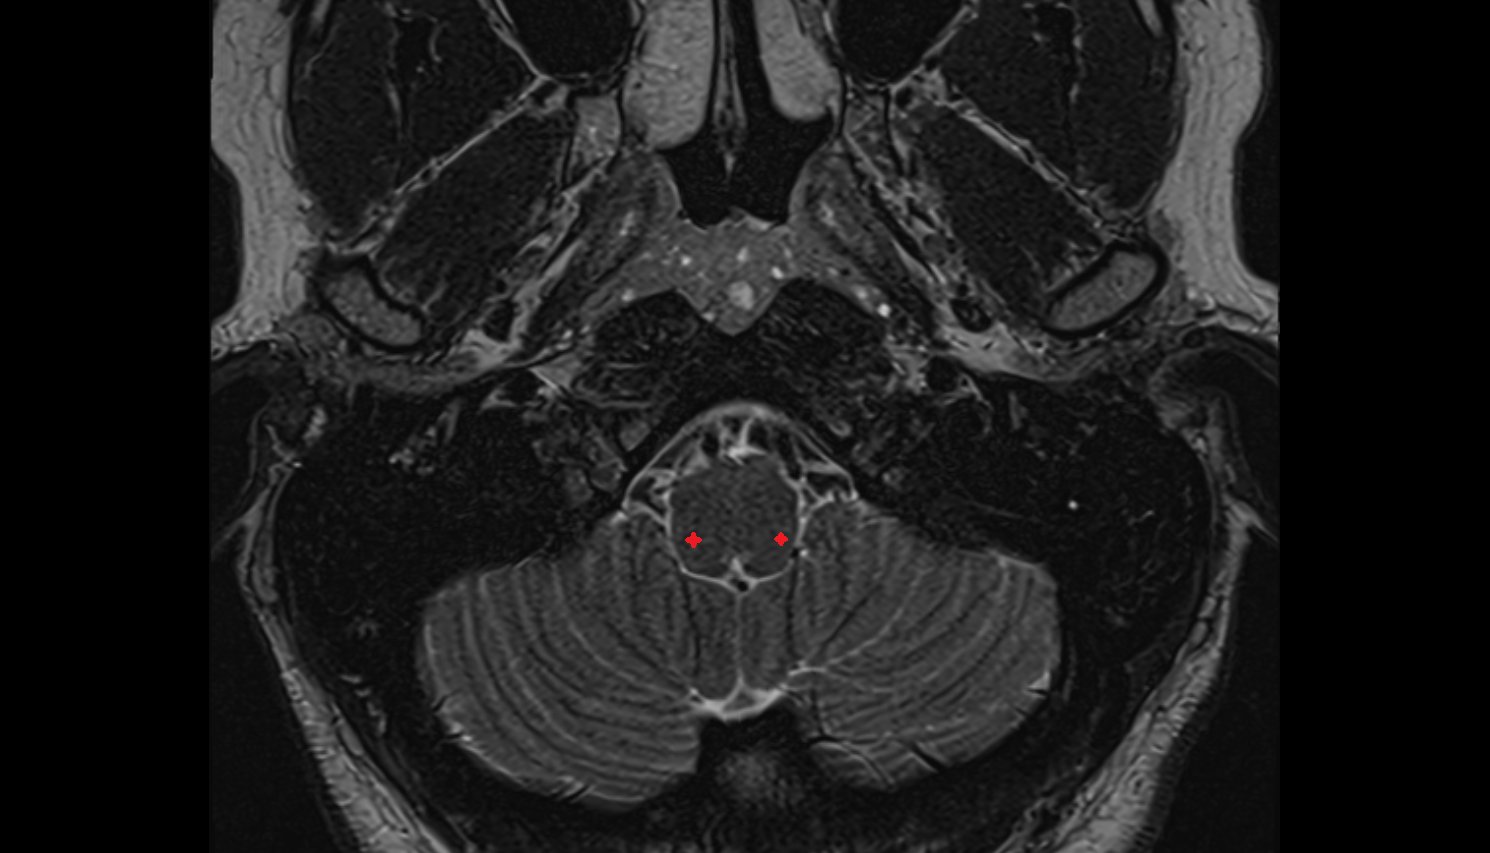

- Cerebellum

- Flocculus

- Crus I of ansiform lobule of cerebellum

- Crus II of ansiform lobule of cerebellum

- Paramedian lobule (HVII) of cerebellum

- Simple lobule (HVI) of cerebellum

- Anterior quadrangular lobule (HV) of cerebellum

- Anterior quadrangular lobule (HlV) of cerebellum

- Biventral lobule (HVIII) of cerebellum

- White matter of cerebellum (Arbor vitae)